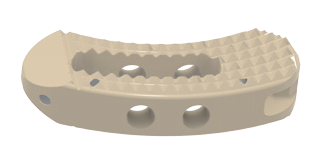

Sistema de cages para fusão intersomática, com diferentes modelos (Coales-P, C, M, T, L e Mesh), em PEEK, com marcadores de tântalo para melhor visualização e adesão óssea.

- Materiais: PEEK (ASTM F2026), Tântalo.

- Medidas: Diversas opções de altura, largura e ângulo de lordose.

- Usos principais: Fusão espinhal lombar e cervical, oferecendo estabilidade e suporte biomecânico.

Design anatômico • Radiotransparente • Marcadores de tântalo para visualização • Reduz risco de subsistência